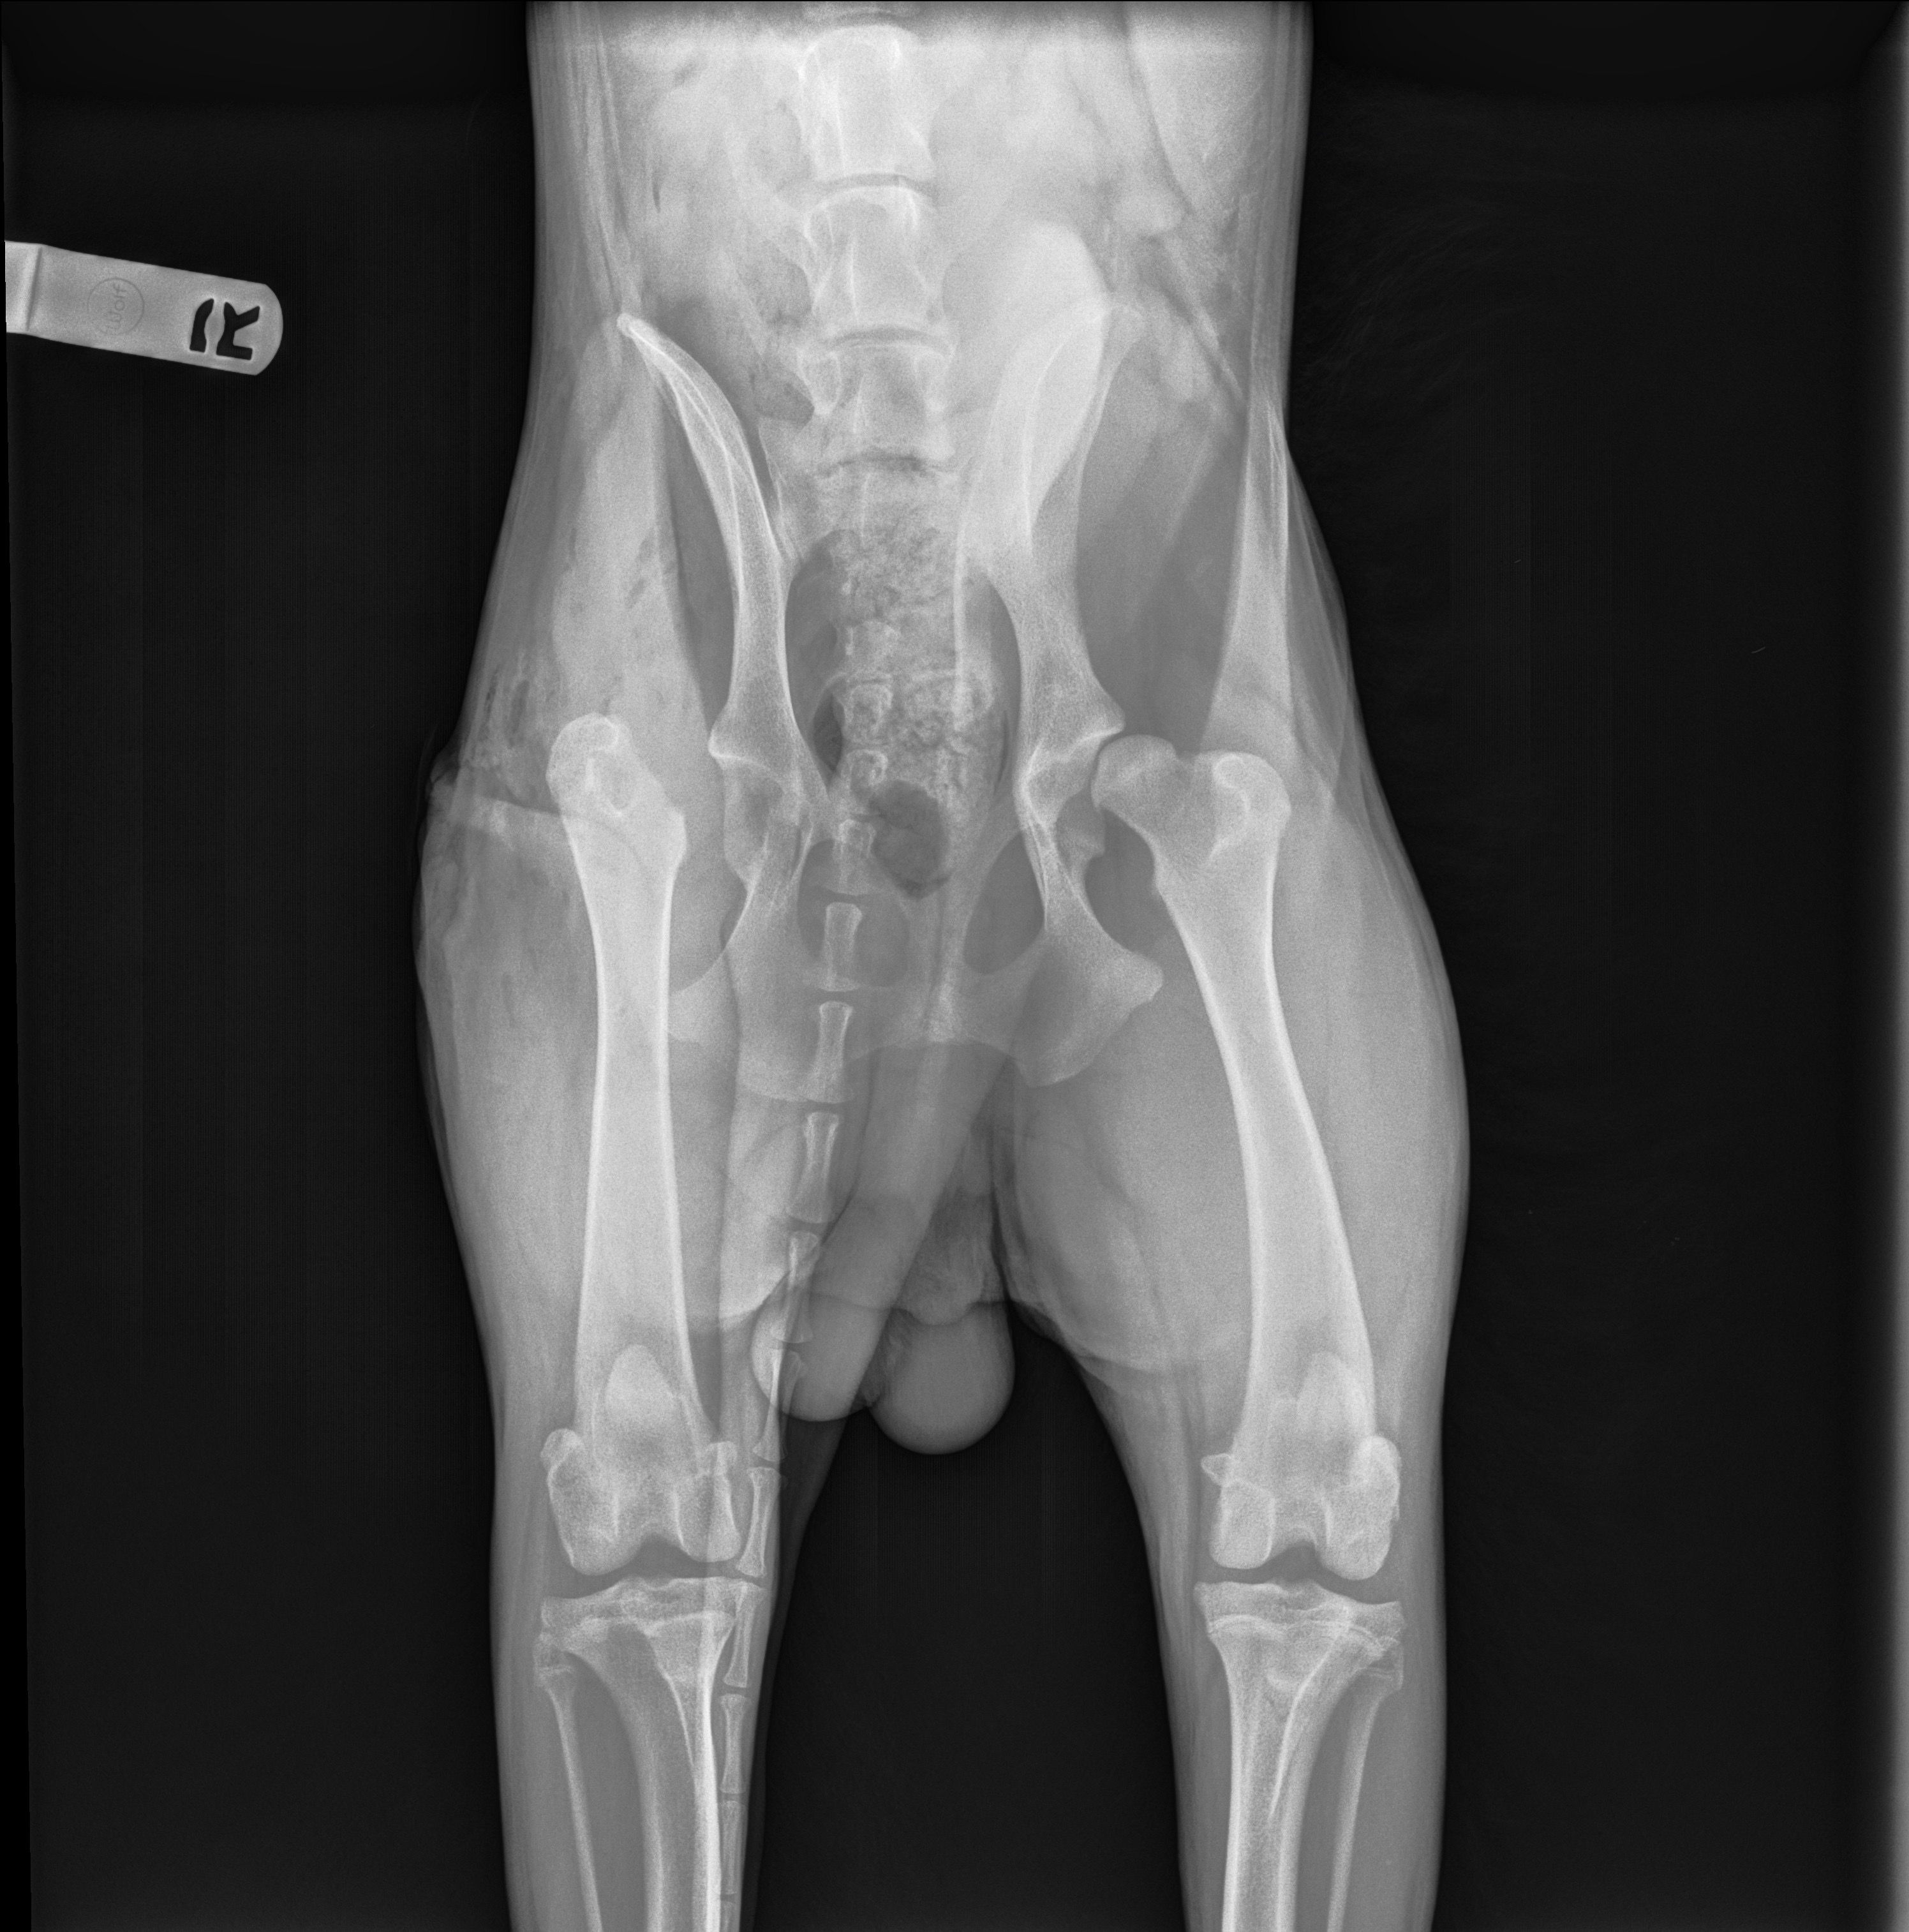

Hello everyone! This is my first time ever making a gofundme and it’s for my special boy Kuma. He had to have an FHO surgery back in November 2024 due to, what I assume, was from his sister going down the stairs too fast behind him and might have ran into him. Took him in when I noticed the slight limp and they saw that his femur was dislocated from the hip and I believe they told me that it might’ve been fractured as well. Luckily I was able to use CareCredit to pay for the surgery to be done within a few days, I didn’t want him to walk on that any longer. He has healed up really well, he has a bit of an irregular gait but that’s alright as long as he isn’t in pain.